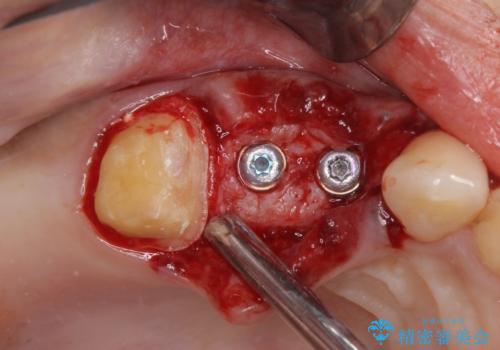

破折した歯を抜去し、インプラントによる補綴を行うこととしました。

治療開始時は右上奥歯と前歯のみが気になっていたのですが、その後下顎左右の奥歯に強い痛みや銀歯の脱離などが頻発し、問題のあるところは全て治療を行うこととしました。